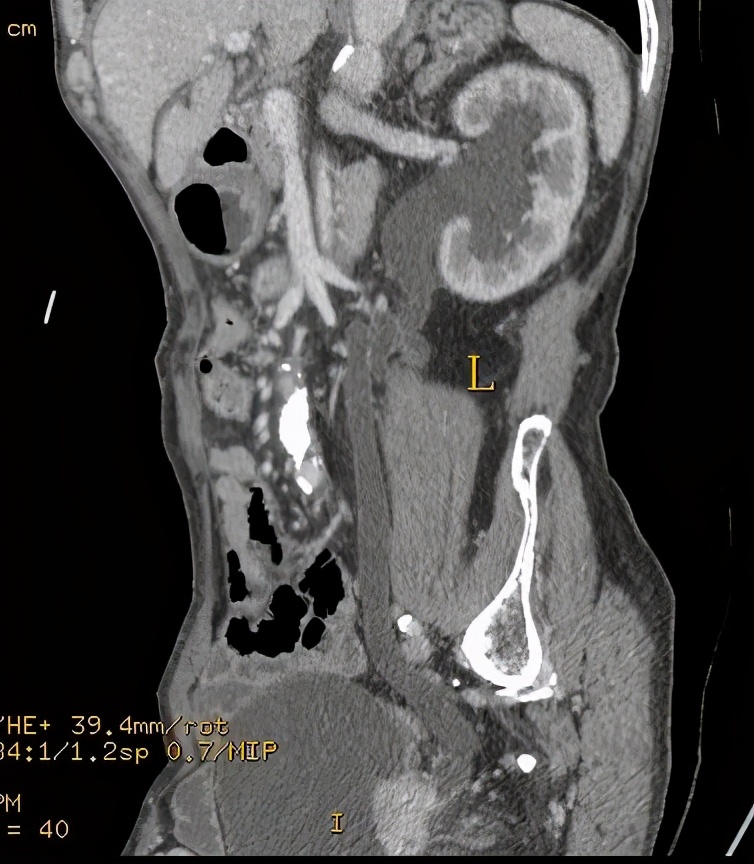

上图所示,(左侧)肾盂癌,压迫(左侧)输尿管上段。